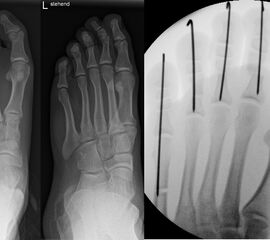

In der minimalinvasiven Fußchirurgie ist es unabdingbar, die Fräse in ihrer Position zum Knochen radiologisch zu kontrollieren, damit vulnerable Wachstumsfugen oder angrenzende Gelenke nicht verletzt werden. Zu diesem Zweck werden mit einem Bildwandler während der Operation die genaue Position der Fräse und der Osteotomieverlauf überprüft, was die Strahlenbelastung im Vergleich zu offenen Verfahren erhöht. Diese Strahlenbelastung hat potenziell einen schädigenden Einfluss auf den noch blutbildenden Knochen von Heranwachsenden. Gesicherte Landmarken am Fuß können die notwendige Zahl der Röntgenbilder und damit die Strahlung minimieren. Ist es erforderlich, mehrere Knochen zu osteotomieren, wie zum Beispiel im Bereich der Kleinzehen, werden anhand der Landmarken kleine Injektionsnadeln auf Höhe der geplanten Osteotomien vorgelegt und radiologisch im Bildwandler (BV) dokumentiert (Abb. 11). Ein solches Bild schafft eine gute Orientierung, sodass auf radiologische Kontrollen intraoperativ weitestgehend verzichtet werden kann.

Abb. 11: Lokalisation mehrerer Stichinzisionen mit einem Röntgenbild.